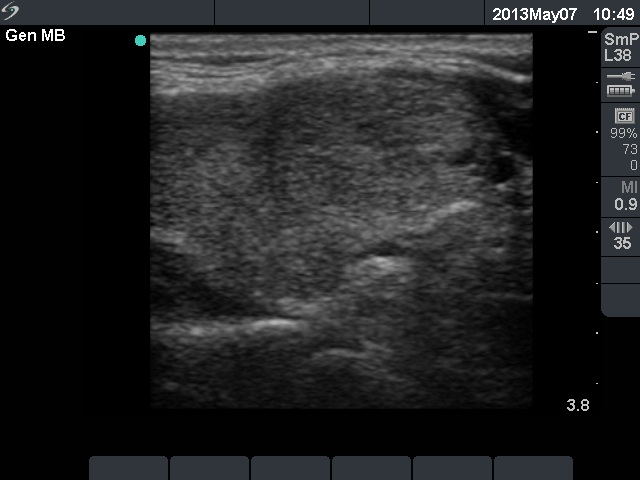

Ethanol sclerotherapy: non-toxic solid nodules - Case 5

Ten years after the therapy (ultrasonographic picture 2)

Right lobe, longitudinal scan.